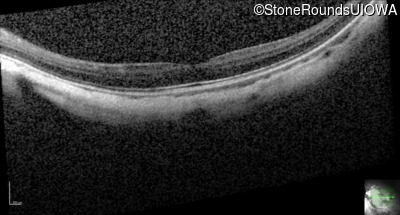

AR CSNB, normal fundus (IA2fiii)

Age at visit: 16 years

This 16 year old male has had poorer vision in dim light than his siblings since childhood. He has also been very myopic since childhood and is currently wearing -14.00 diopter spectacles. The maximum combined response of the electroretinogram reveals a selective loss of the b-wave.

AR CSNB, normal fundus TRPM1 Lys18 del18aAGGTGAGTGAGCTTTGCC Tyr72Cys TAT>TGT AR